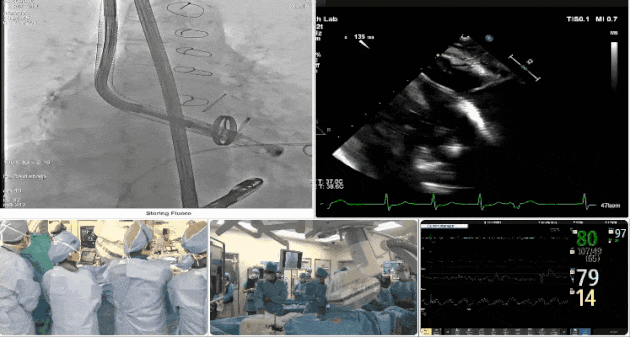

術(shù)中DSA顯示起搏器導線的干擾,右心室造影確定瓣環(huán)位置,操作空間小

術(shù)后超聲顯示人工瓣膜穩(wěn)定性良好,瓣葉啟閉正常

手術(shù)過程

術(shù)者采用經(jīng)右側(cè)頸靜脈入路的方式將輸送器送入患者心臟內(nèi),在TEE及DSA引導下調(diào)整輸送器頭端角度,使得輸送器與三尖瓣瓣環(huán)平面垂直。在輸送器進入右心室后釋放室間隔錨定裝置,而后釋放瓣葉夾持件(2個耳片結(jié)構(gòu))成垂直狀態(tài)。在TEE及DSA確定夾持件固定至三尖瓣葉根部且位于右室側(cè)后釋放人工瓣心房側(cè)盤片。隨后調(diào)整瓣膜同軸性以及室間隔錨定件位置(貼合室間隔),前推藏針管并固定,進而釋放室間隔錨定裝置,并再次確認瓣膜位置、穩(wěn)定性及同軸性,合攏輸送鞘后撤出輸送器,最終順利完成LuX-Valve Plus人工三尖瓣瓣膜的植入。